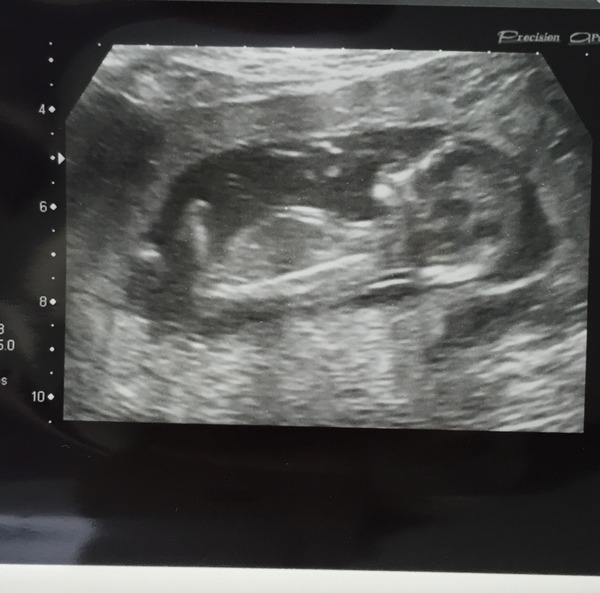

KeepTheHope · 21/01/2016 11:36

Here is a camera shy baby who decided it likes lying the wrong way up and had to be jiggled about. A few days further along than I thought so now 13 weeks today Grin